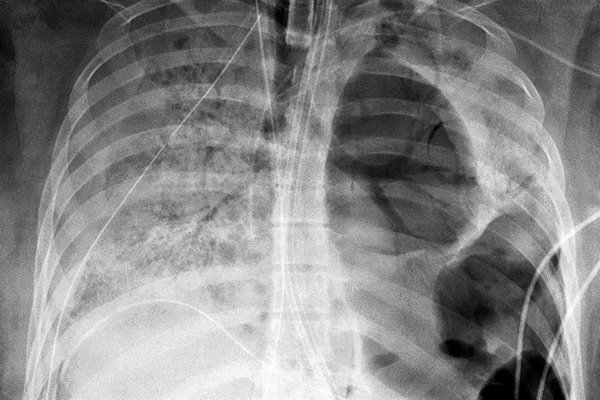

Cada vez hay más pruebas de que la variante Ómicron del coronavirus afecta al tracto respiratorio superior y provoca síntomas más leves que las variantes anteriores, lo que ha resultado en un “desacoplamiento” en algunos lugares entre el aumento de casos y las bajas tasas de mortalidad, dijo el martes un funcionario de la Organización Mundial de la Salud.

“Estamos viendo más y más estudios que señalan que Ómicron está infectando la parte superior del cuerpo. A diferencia de las otras (variantes), que afectan a los pulmones y podrían causar una neumonía grave”, dijo el responsable de incidentes de la OMS, Abdi Mahamud, a la prensa en Ginebra.